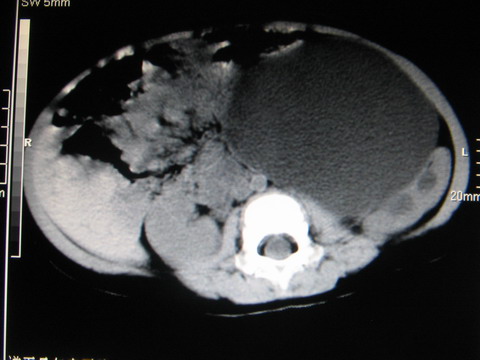

标题: PED0552:男1岁,双肾区CT [打印本页]

标题: PED0552:男1岁,双肾区CT

胎龄5个月时b超示左肾积水,现一岁后复查

先天性巨输尿管畸形

mru检查除外先天性巨输尿管